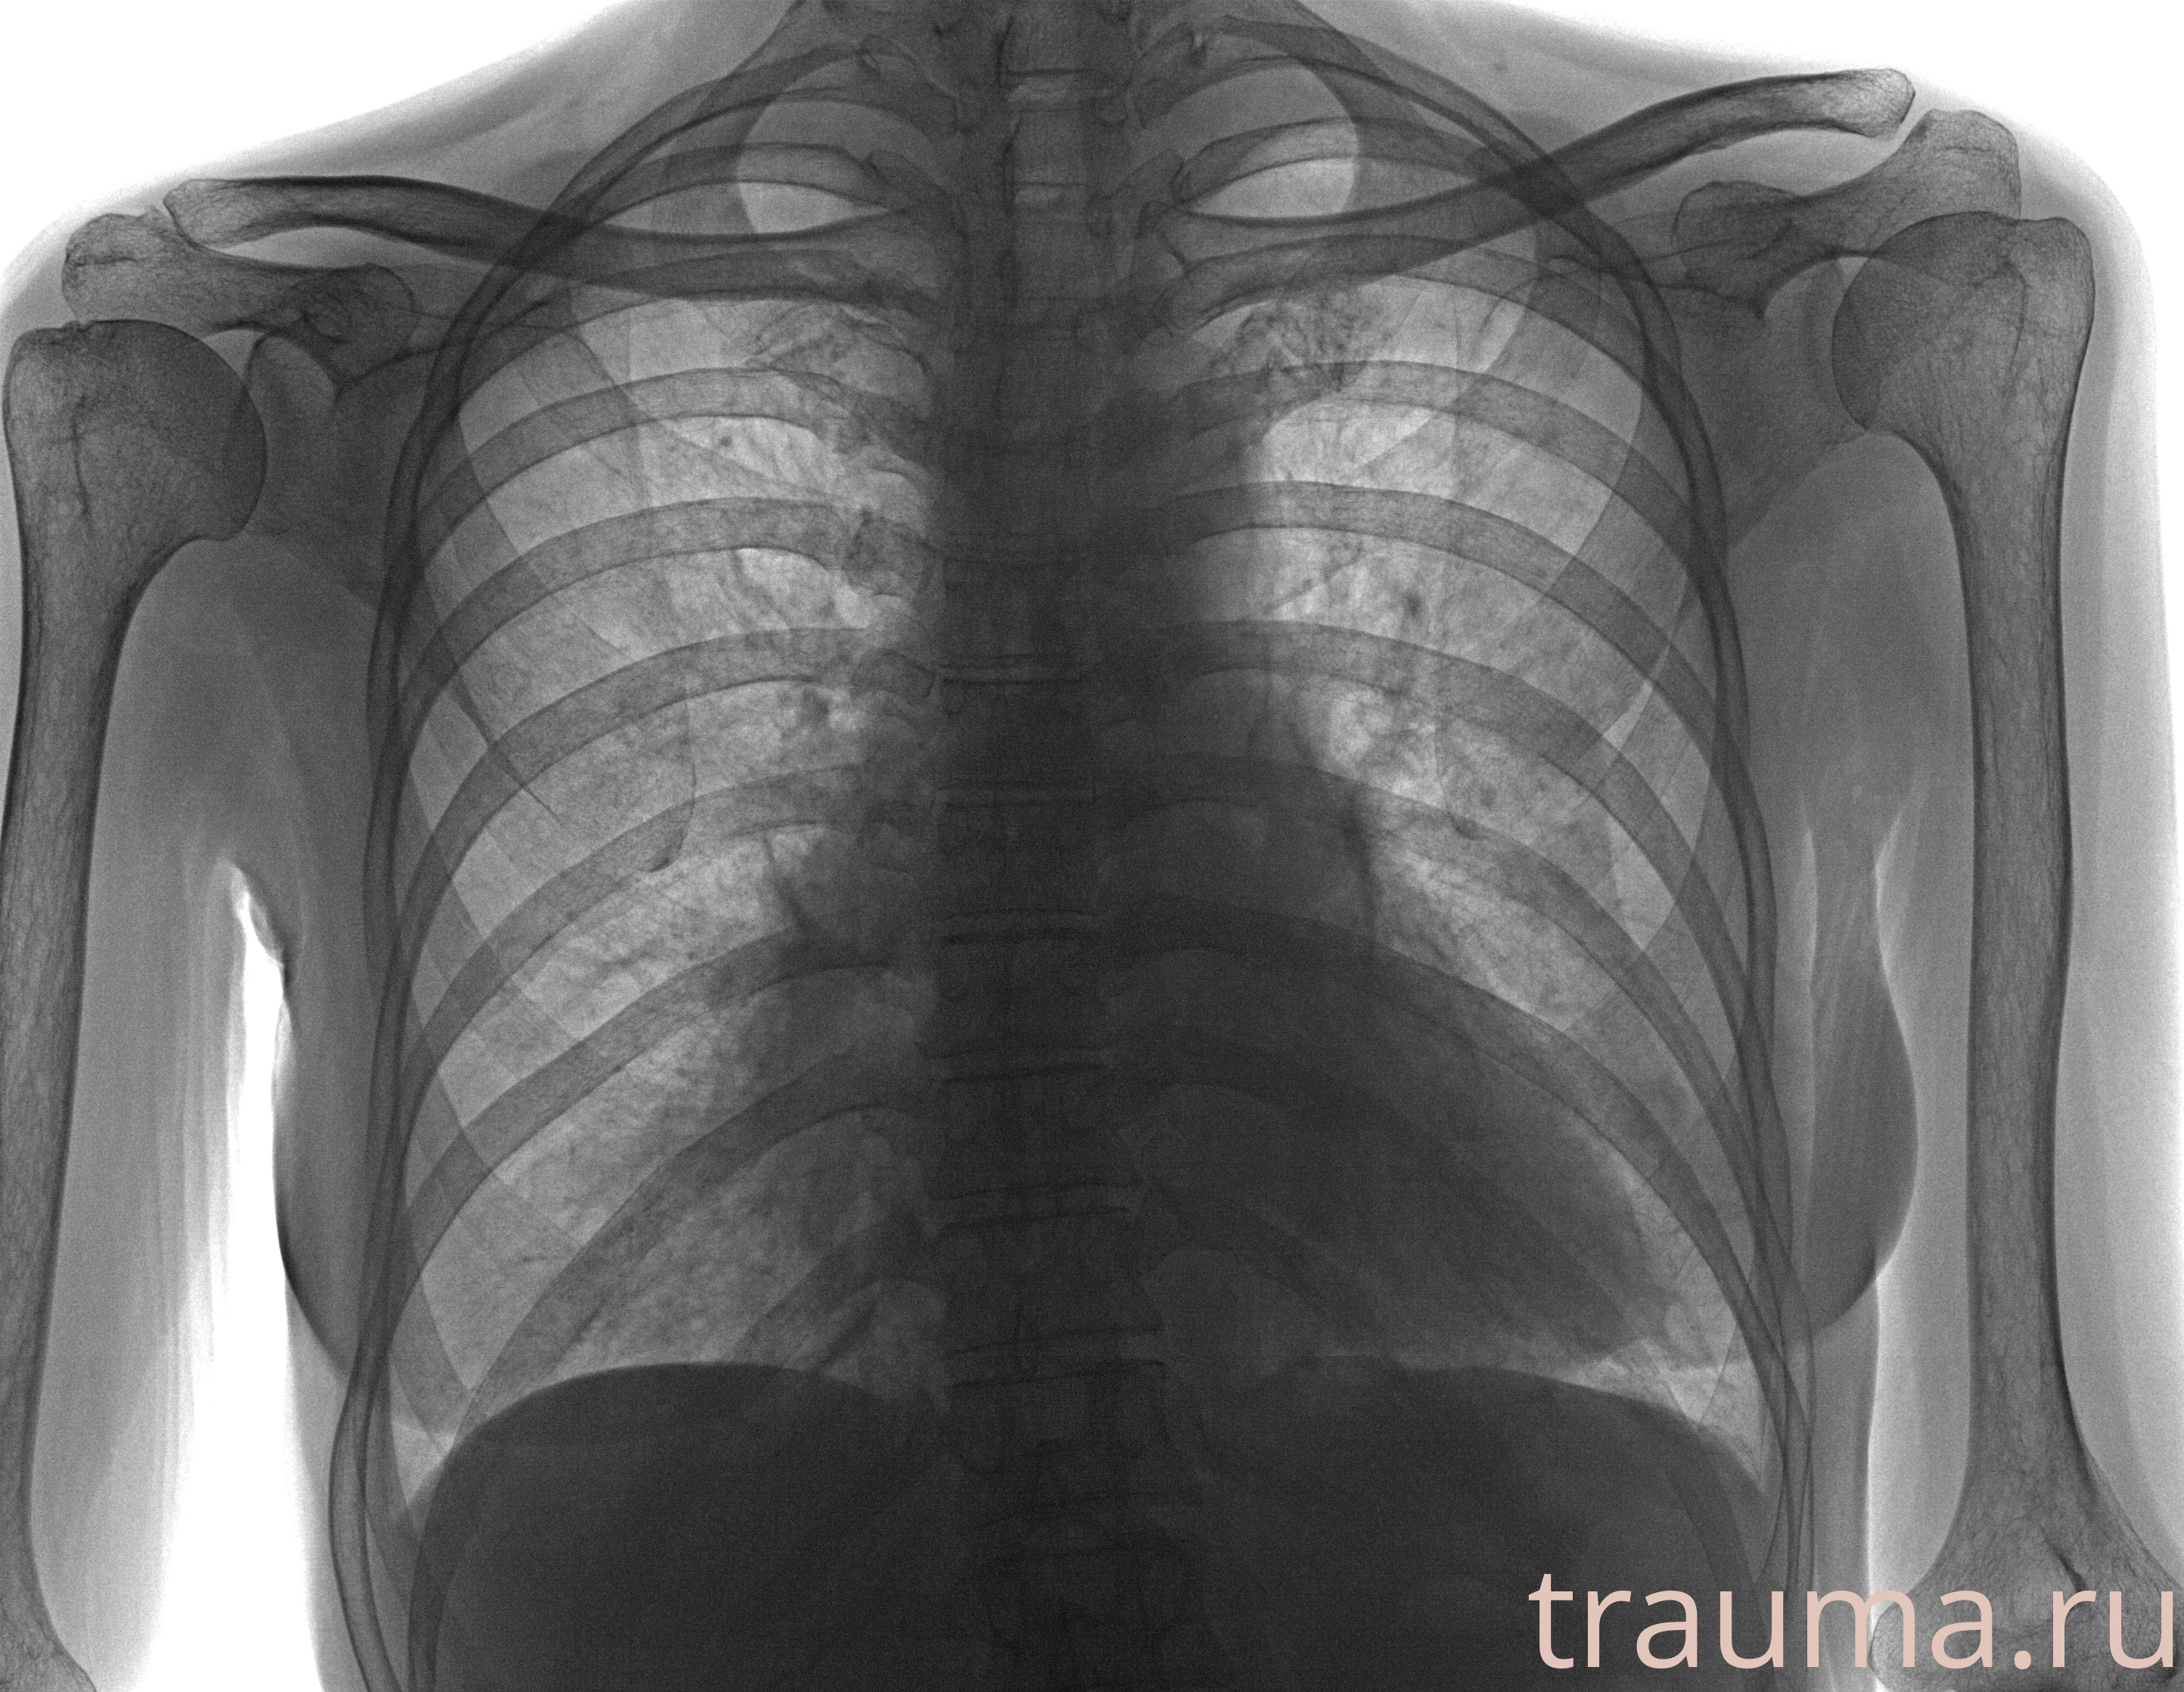

Рентген на дому: по вашему адресу приезжает врач-рентгенолог, травматолог-ортопед с мобильным рентгеновским аппаратом, проводит диагностику травмы или заболевания, делает необходимые рентгенограммы, дает рекомендации по дальнейшему лечению. Получить качественные снимки в домашних условиях возможно благодаря уникальной методике, разработанной МосРентген Центром для института  Склифосовского